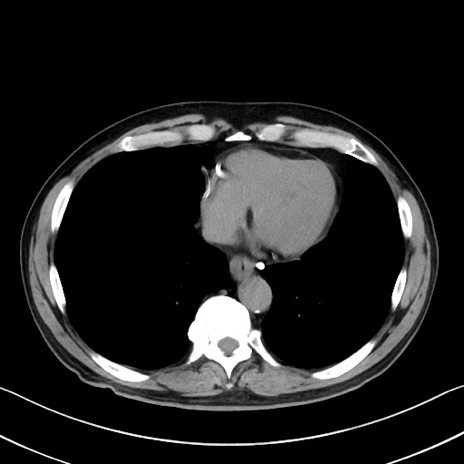

症例35(横断像)

【症例】70歳代 男性

【主訴】腹部膨満、嘔吐

【現病歴】昨日より腹部膨満感出現。本日増悪し、仙痛出現。嘔吐あり、受診。

【既往歴】糖尿病、胆摘後

【身体所見】BP 149/80mmHg、HR 74/min、BT 35.9℃、腹部:膨満、軟、圧痛なし。腸雑音減弱あり。上腹部正中切開瘢痕あり。

【データ】WBC 13500、CRP 1.72